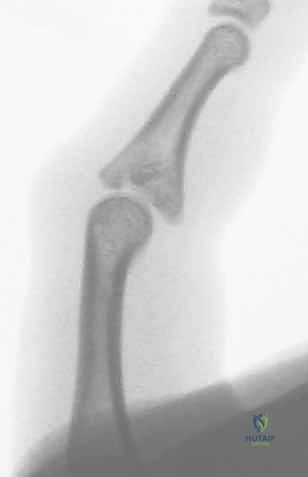

- الخلع الظهري مع كسر (Dorsal Fracture-Dislocation): وهو النوع الأكثر شيوعًا. يحدث عندما تندفع السلامية الوسطى للخلف (نحو ظهر اليد). يترافق عادة مع تمزق الصفيحة الراحية وكسر في الجزء الراحي (السفلي) من قاعدة السلامية الوسطى.

- الخلع الراحي مع كسر (Volar Fracture-Dislocation): أقل شيوعًا ولكنه أكثر تعقيدًا في العلاج. تندفع فيه السلامية الوسطى للأمام (نحو باطن اليد). يترافق مع تمزق الوتر المركزي الباسط وكسر في الجزء الظهري من المفصل.

2. التصوير بالأشعة السينية (X-Rays)

هو المعيار الذهبي الأولي. يجب أخذ صور شعاعية واضحة ومحددة للإصبع المصاب (وليس لليد بأكملها) في ثلاث وضعيات:

* الوضعية الأمامية الخلفية (AP): لتقييم المحور الجانبي للإصبع والبحث عن شقوق عظمية.

* الوضعية الجانبية الحقيقية (True Lateral): هي الصورة الأهم على الإطلاق. من خلالها يتم تحديد حجم القطعة العظمية المكسورة، ومقدار انزياح المفصل. يبحث الجراح الماهر هنا عن علامة "V-Sign" الشهيرة، والتي تدل على عدم تطابق الأسطح المفصلية ووجود خلع جزئي غير مستقر.